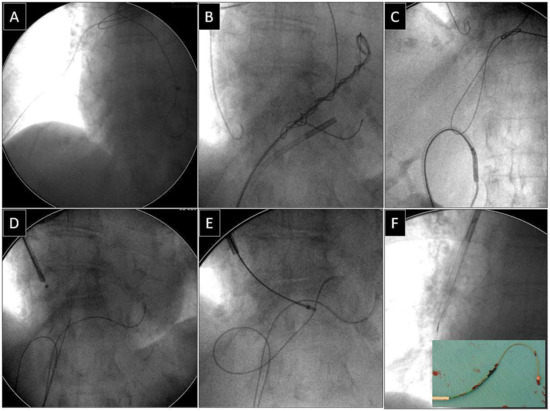

2.2.5. Extraction of Leads with Their Proximal Ends Migrated into the Cardiovascular System